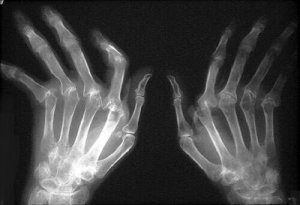

Asiantuntijoiden mukaan niveltulehduksia on olemassa yli sata erilaista tyyppiä. Kaksi niistä on tavallisimpia: nivelrikko ja nivelreuma. Molemmat ovat kivuliaita sairauksia, jotka aiheuttavat paljon kärsimystä, tulehduksia, punaisuutta ja jäykkyyttä – oireita, joista voi helposti tulla kroonisia.

Äkillinen turvotus on tavanomaista, esimerkiksi sormien puutuminen, tulehtuminen ja muuttuminen punaisiksi. Älä jätä tätä huomioimatta. Mitä nopeammin alat hoitaa niveltulehdusta, sen parempi.